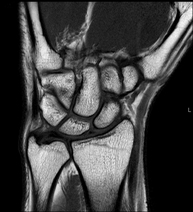

Exploració per a l'estudi de lesions en els tendons, els músculs i els nervis perifèrics. La durada aproximada és de 18 minuts. No utilitza radiació ionitzant. - RM Canell /carp

Exploració per a l'estudi de lesions en els tendons, els músculs i les articulacions. Molt útil per a la valoració de petites fractures inadvertides, lesions de lligaments i processos inflamatoris i degeneratius (artritis i artrosi). La durada aproximada és de 20 minuts. No utilitza radiació ionitzant. - RM de Mà / dits